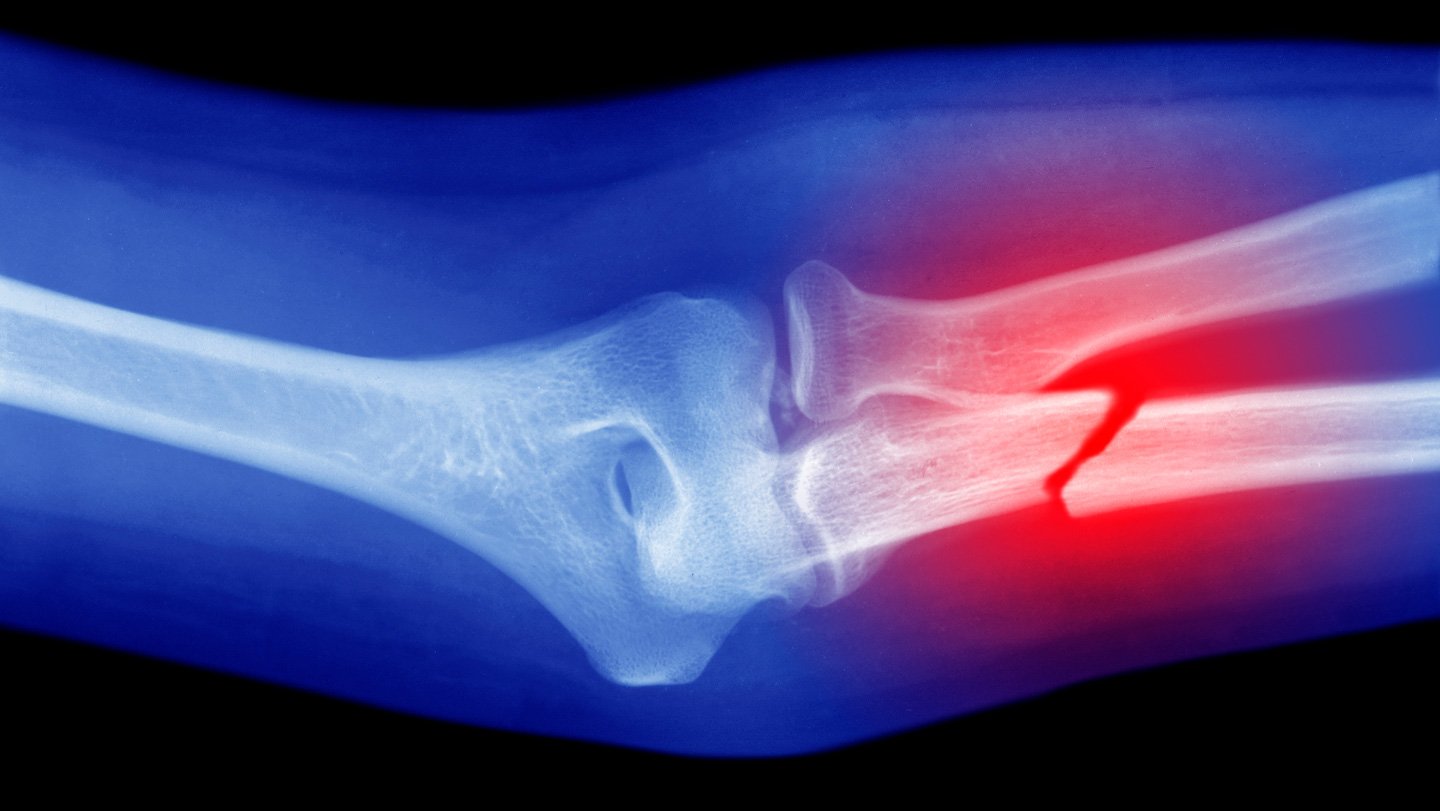

A handheld device can apply synthetic bone grafts directly at the site of a defect or injury without the need for prior imaging or fabrication.

Researchers demonstrated the technology by modifying a hot glue gun to 3-D print the material directly onto bone fractures in rabbits. Instead of using a regular glue stick, they employed a specially made “bioink,” the team reports September 5 in Device.

“We can save time, cost and complex procedures [compared with those] required in conventional 3-D printing–based bone graft fabrication,” Lee says. Usually, scans and measurements of injuries are needed to build bonelike implants to exact specifications, a process that can take days and delay surgeries.

Lee and his colleagues tested the glue gun and bioink on femoral bone fractures in rabbits. Comparing results from rabbits receiving the therapy with a control group receiving regular bone cement, the team found that the former group had better healing and regeneration of bone tissue. The animals also showed no signs of infection during the 12 weeks following surgery.